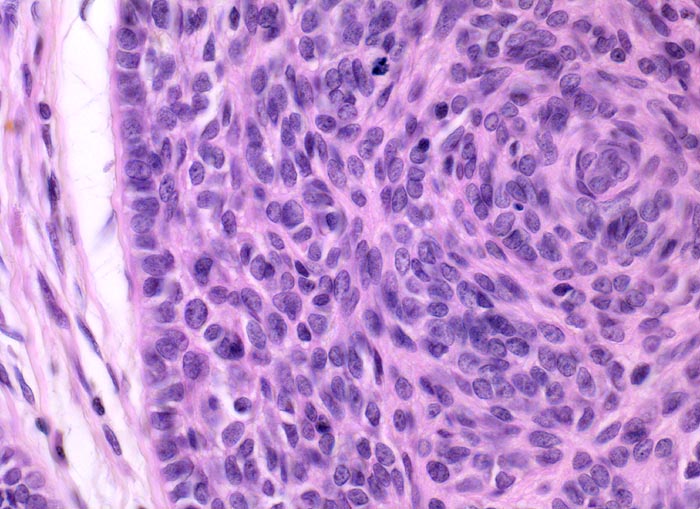

Basaliom

maligner Tumor

Haut, Kopf

Solider Tumor. Die Tumorzellen sind am Rand der Zellplatte parallel ausgerichtet, im Zentrum liegen sie ungeordnet und bilden einen angedeuteten Wirbel. Die Tumorzellkerne sind leicht hyperchromatisch und recht monomorph. Spärlich vorhandenes basophiles Zytoplasma und unscharfe Zellgrenzen. Retraktionsartefakt zwischen Tumor und Stroma.

Derber weisser, leicht erhabener Knoten an der Nase.

Histologie

400